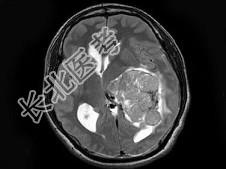

- 单项选择题男,27岁, 一过性黑矇发作半年伴记忆力下降,听觉性失语, 双眼同向性右侧视野缺损,无头痛、呕吐, MRI平扫及增强扫描,最可能的诊断为 ( )

A、侧脑室脑膜瘤

B、侧脑室室管膜瘤

C、侧脑室乳头状瘤

D、侧脑室星形细胞瘤